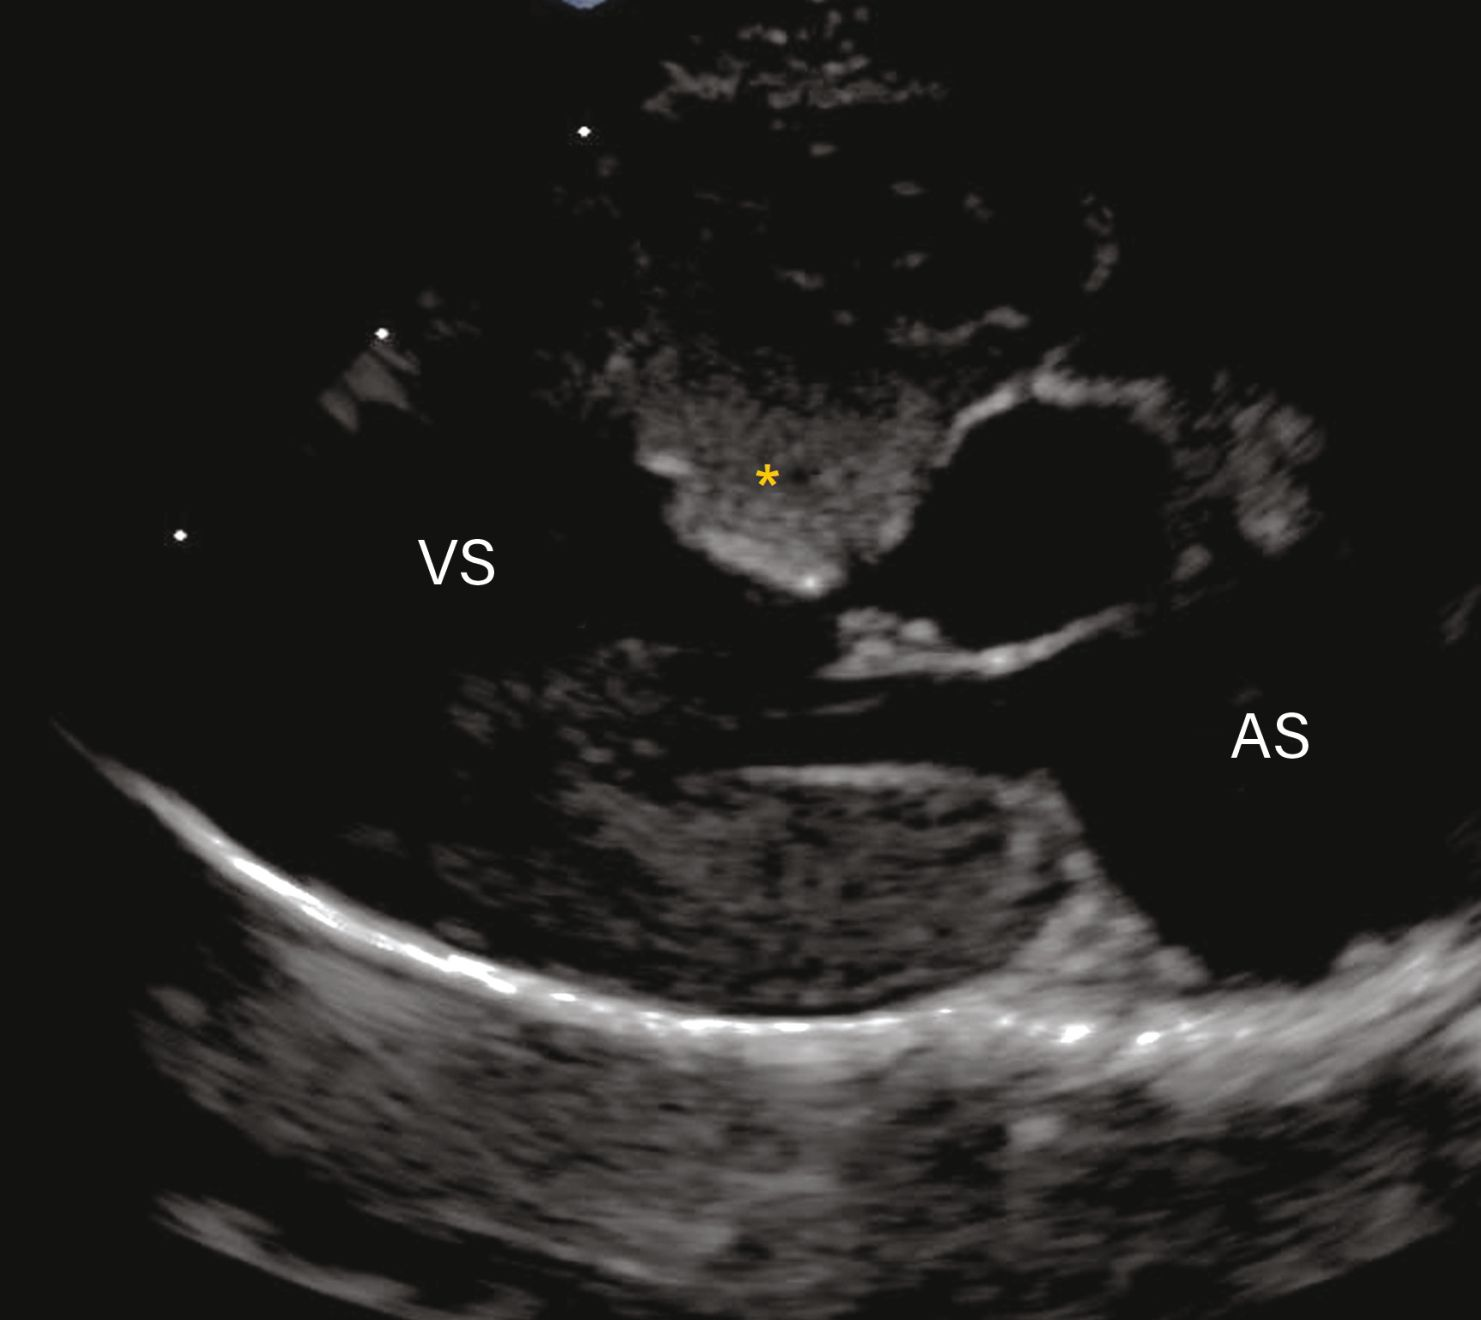

Vizualizare parasternală dreaptă în ax lung cu 5 camere care arată hipertrofia localizată la nivelul septului bazal (*) ca fiind cauza LVOTO.

Figura 3b. . La pisicile cu CMH suflurile sunt cel mai adesea rezultatul obstrucției tractului de ejecție al ventriculului stâng (LVOTO). Vizualizare parasternală dreaptă în ax lung cu 5 camere care arată hipertrofia localizată la nivelul septului bazal (*) ca fiind cauza LVOTO.

Credit: Catheryn Partington Joanna Dukes-McEwan